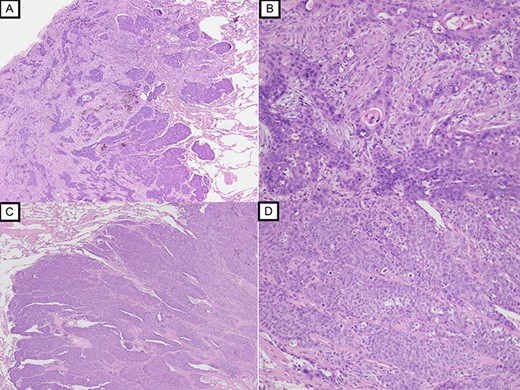

Histopathological examination with HE staining revealing squamous cell carcinoma in S1 nodule (original magnification ×20 (A), ×100 (B)); histopathological examination with HE staining revealing poorly differentiated squamous cell carcinoma in S2 nodule (original magnification ×20 (C), ×100 (D)).